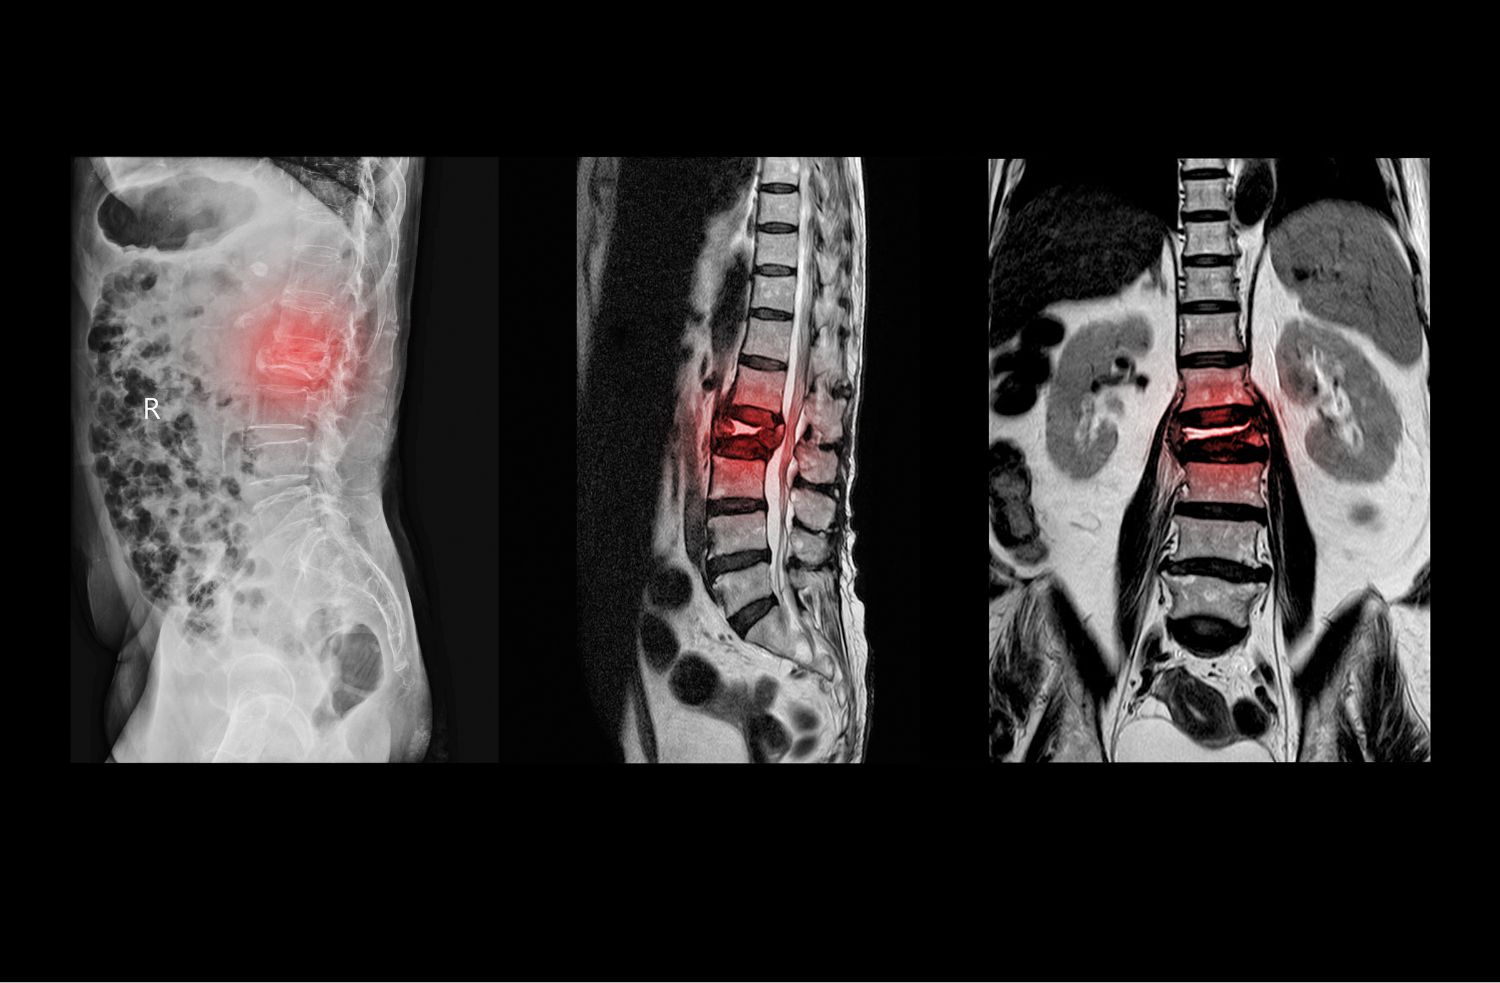

영상검사

척추관 협착증의 정확한 진단을 위해서는 영상검사가 필요합니다. 대표적인 영상검사로는 X-선, CT, MRI 등이 있습니다. 이러한 검사를 통해 척추의 구조와 크기, 뼈와 디스크의 이상 등을 확인할 수 있습니다.